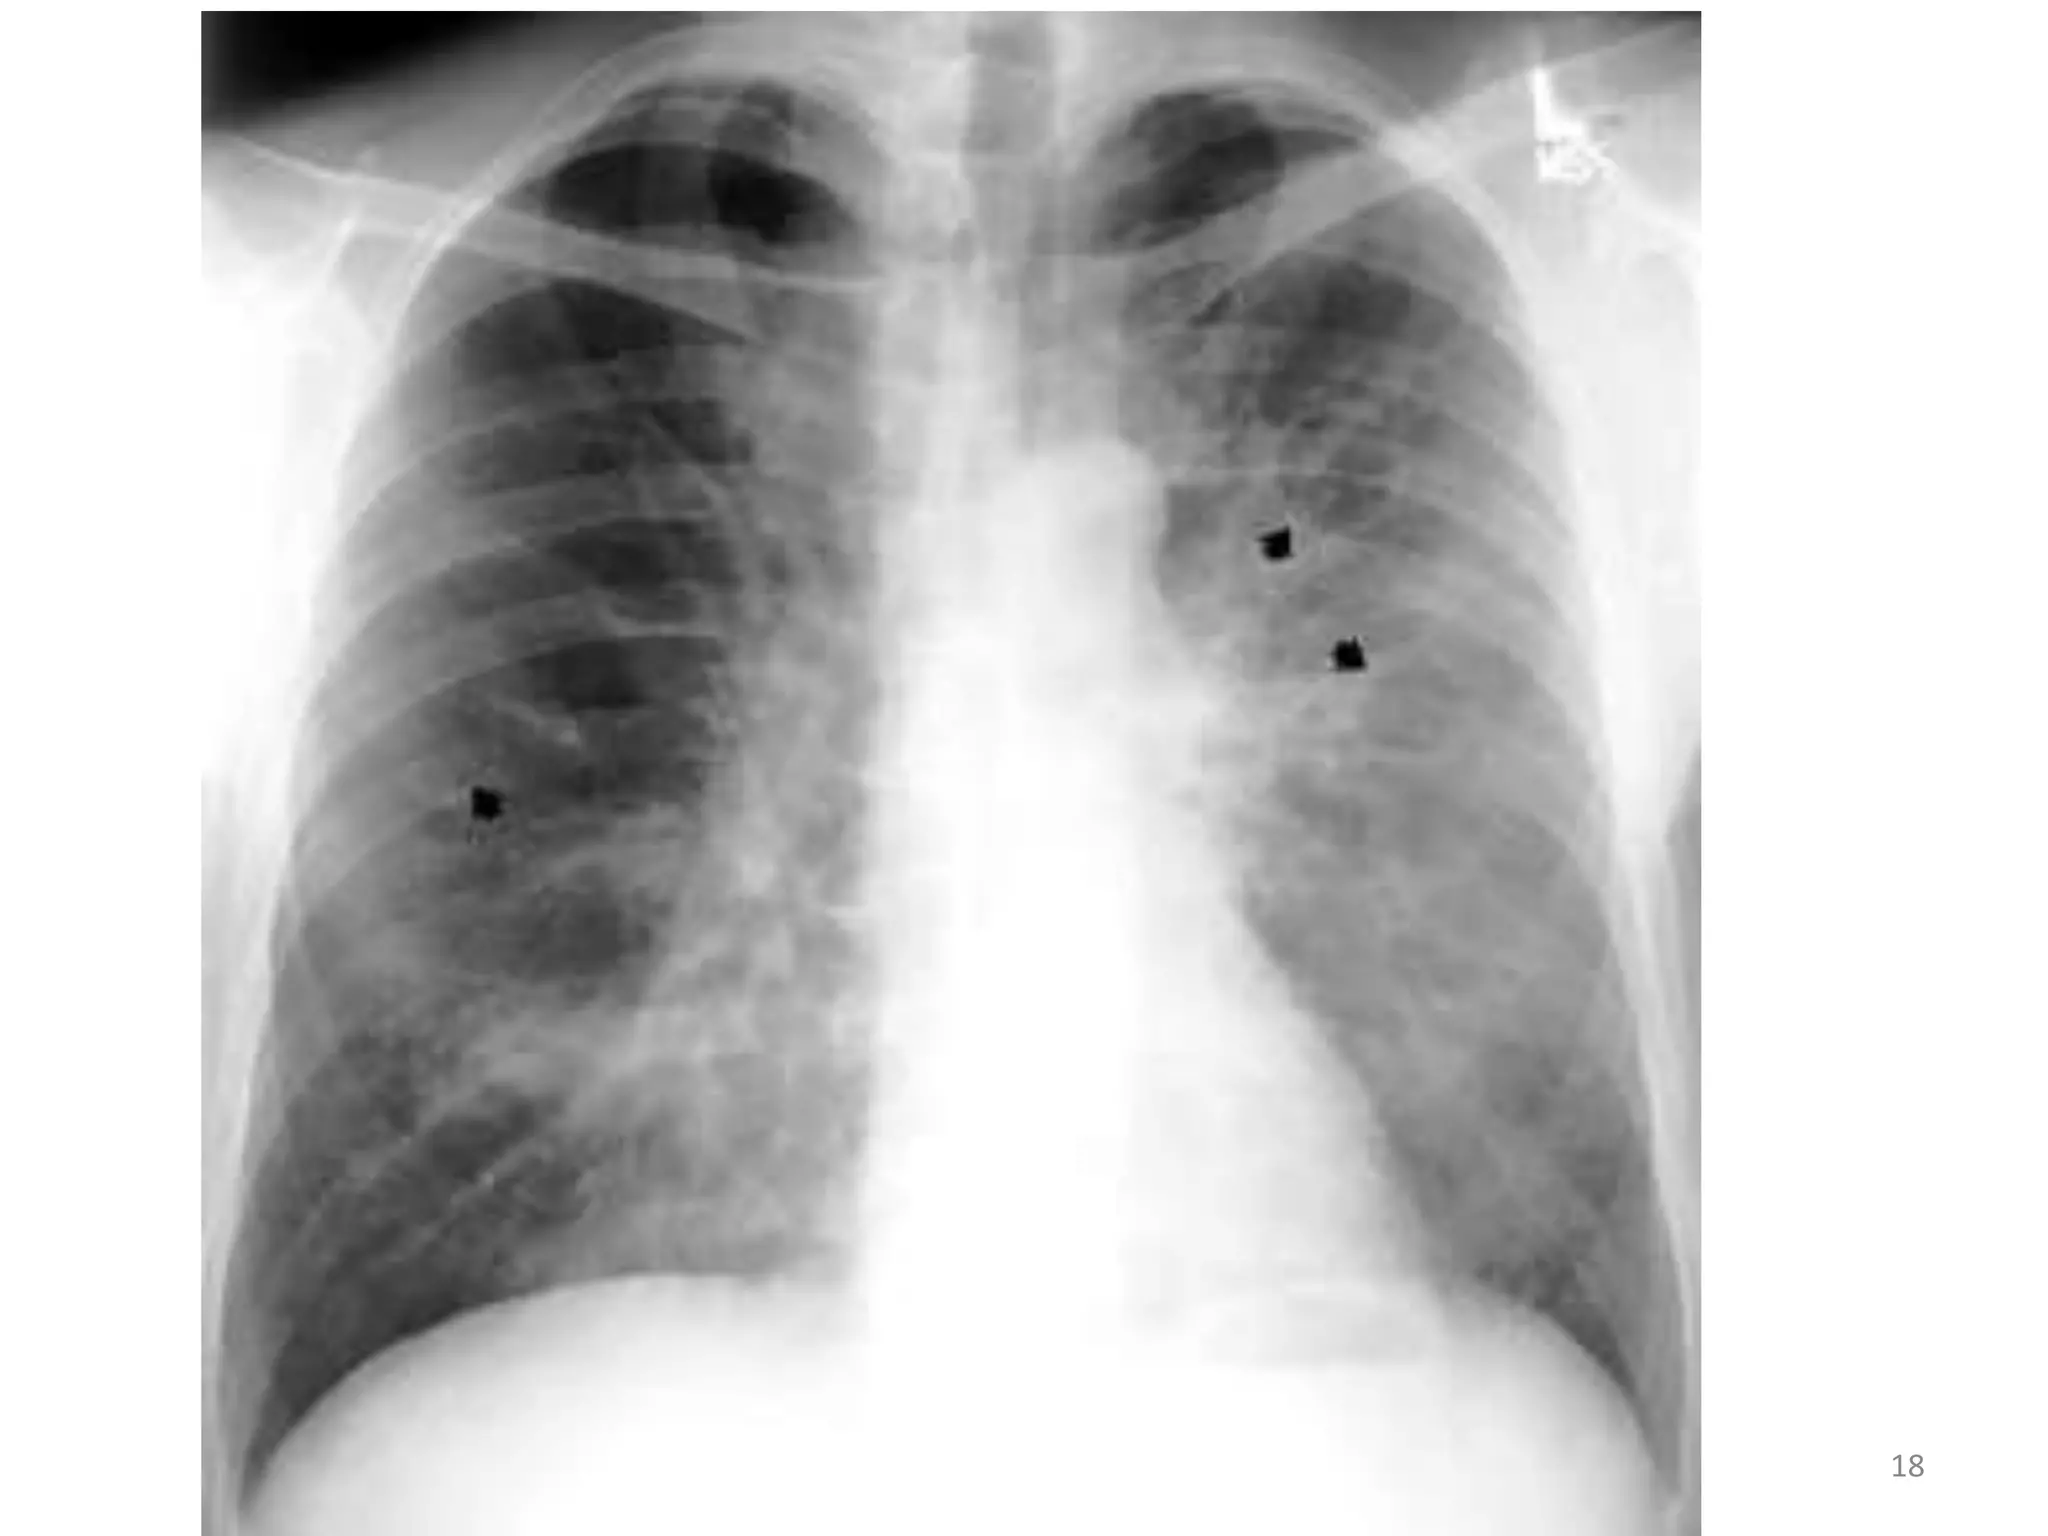

PNEUMOCYSTIS JIROVECI INFECTION

• PNEUMOCYSTIS Pneumonia (PCP) was once

the hallmark of AIDS.

• single most common cause of pneumonia in

patients with HIV and is likely the etiologic

agent in 25% of cases of pneumonia in

patients with HIV infection.

• PCP presents with non productive cough or

with scanty white sputum production.

• Patients complain of characteristic

retrosternal chest pain , described as sharp or

burning type, and worsens on inspiration.

• The disease usually has an indolent course

with weeks of vague symptoms.

• #18 . The standard treatment for PCP or disseminated pneumocystosis is trimetlaoprim/sulfamethoxazole (TMP/SMX). A high (20-85%) incidence of side effects, particularly skin rash and bone marrow suppression, is seen -with TMP/SIVIX in patients with HIV infection. Alternative treatments for mild to moderate PCP include dapsone/ trimethoprim, clindamycin/primaquine, and atovaquone. IV pentamidine is the treatment of choice for severe disease in the patient unable to tolerate TMP/SMX

• #19 X ray revealing bilateral, predominantly central, granular opacities and 3 thin-walled air-containing cysts (pneumatoceles) (arrows). This combination of findings is strongly suggestive of Pneumocystis jiroveci pneumonia, which was microscopically confirmed by examination of bronchoalveolar lavage fluid.